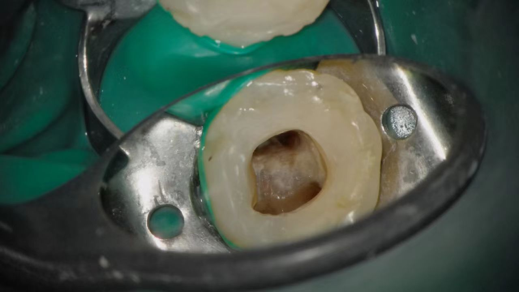

4K超清图像效果

企业微信截图_17496941442680.png